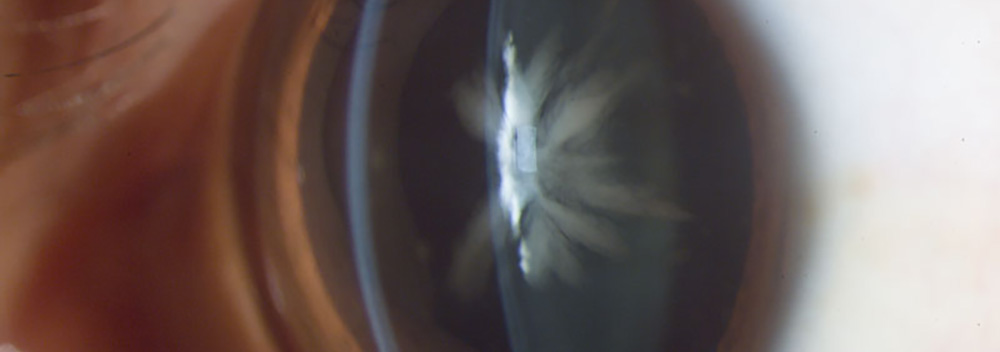

Catarata Congénita, Fotografía, Instituto Barraquer de América